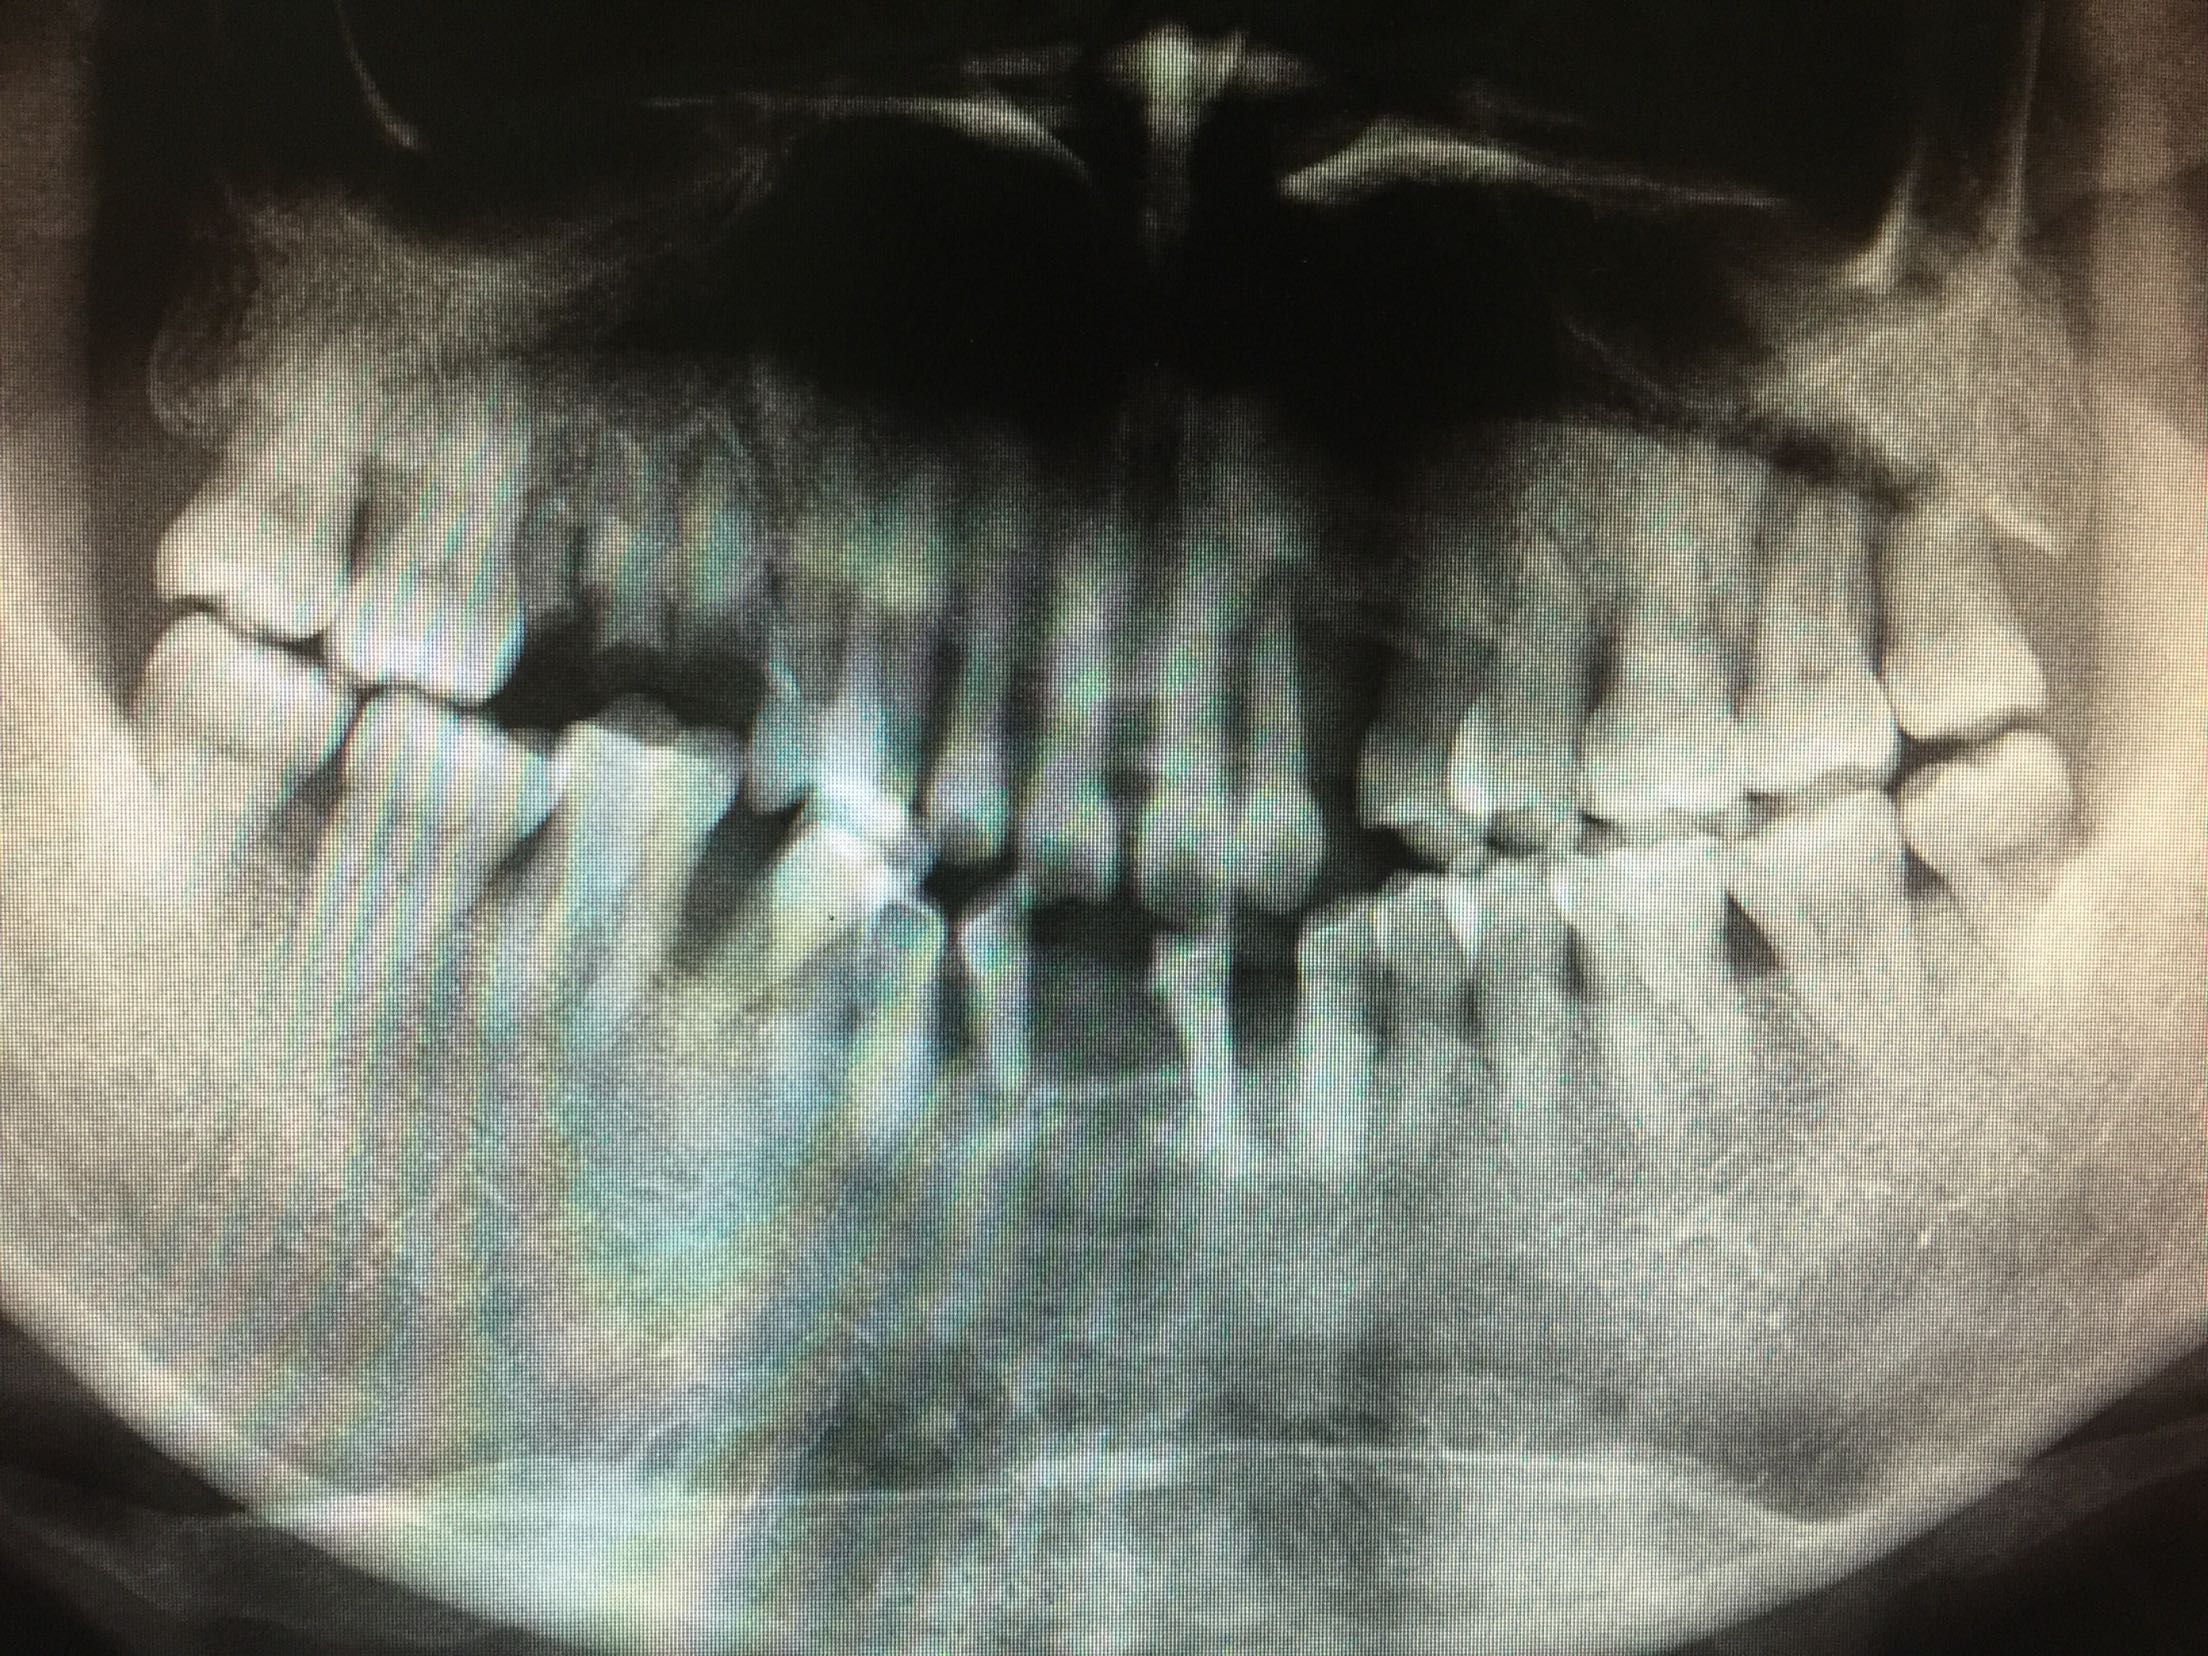

检查:全口卫生差,牙石++,软垢+,牙龈红肿,有退缩。口内多颗牙缺失,46牙伸长,松-+。 X线:46牙伸长,未行根管治疗,根尖区未见暗影。

诊断:46牙伸长 全口牙周炎 牙列缺损 治疗计划:46牙去髓术 全口洁治 择期修复缺牙区 治疗:碧蓝麻局部浸润,46牙去净龋坏,开髓揭髓顶,探查根管4根,牙髓摘除术,k挫初步预备,根管测长仪测量根管长度,各根管内导入根管润滑剂EDTA,Protaper镊钛器械预备根管,冲洗,超声荡洗,水溶性氢氧化钙充填根管,暂封,约复诊。 复诊:一周后,诊间无不适,46牙暂封完好,冷-,探-,叩-,不松。 试主尖,